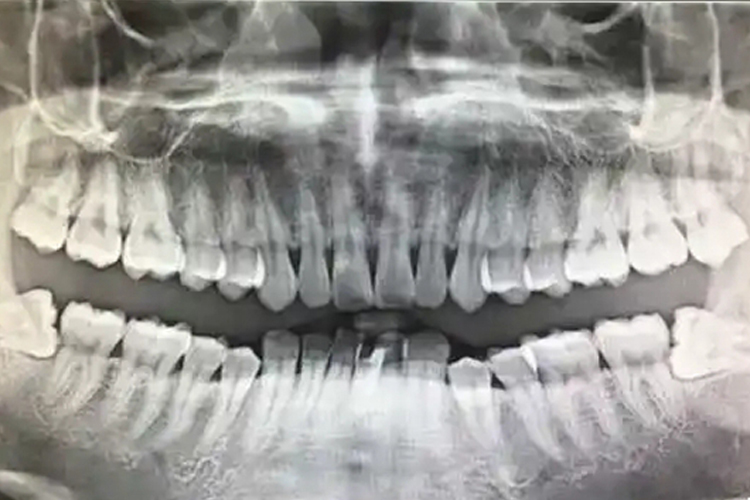

一般情况下,根据阻生智齿,即下颌第三磨牙在颌骨内的深度,可分为高位,中位及低位三类。

高位:对于高位阻生智齿,牙的最高部位平行或高于(牙合)平面。

中位:对于中位阻生智齿,牙的最高部位低于(牙合)平面,但高于第二磨牙的牙颈部。

低位:对于低位阻生智齿,牙的最高部位低于第二磨牙的牙颈部。对于骨埋伏阻生,即牙全部被包埋于骨内现象,也属于低位阻生智齿。